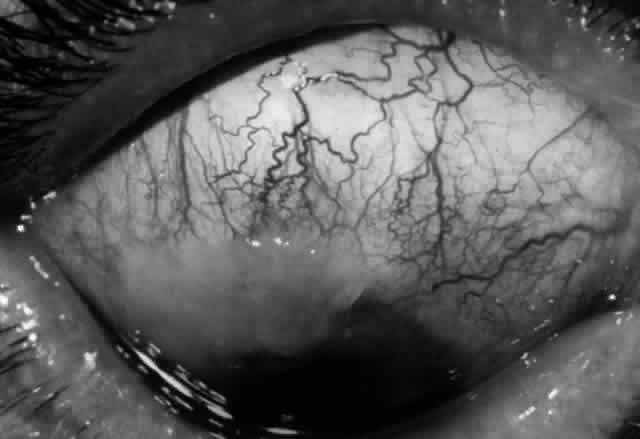

Clinically, the ocular disease in cicatricial pemphigoid (OCP) may present unilaterally in the form of a chronic, recurrent catarrhal conjunctivitis, but it eventually becomes bilateral. Subepithelial fibrosis is characteristic of stage 1 of OCP (Fig. 7). Stage 2 shows fornix foreshortening (Fig. 8), and symblepharon formation is the hallmark of stage 3 (Fig. 9). Stage 4, end-stage disease, is characterized by ankyloblepharon and surface keratinization (Fig. 10). Obstruction of the lacrimal ductules and meibomian gland ducts eventually produces an unstable tear film and progressive sicca syndrome, but it is to be emphasized that OCP is not a dry-eye syndrome until late in the disease course.20 Trichiasis and entropion occur because of the subepithelial fibrosis, with eventual keratopathy, corneal neovascularization, and corneal ulceration and scarring.20

Fig. 7. Stage 1 cicatricial pemphigoid, with cicatrizing conjunctivitis, and fine striae-type areas of subepithelial fibrosis, but without evidence of shrinkage of the conjunctiva.